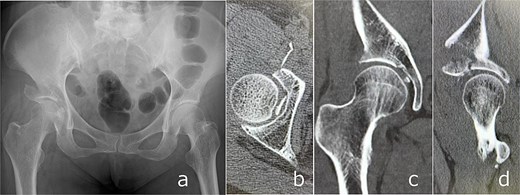

Closed reduction was performed under sedation. Post-reduction imaging showed incarceration of the femoral head fragment within the acetabulum and partial deficiency of the anterior roof arc (Fig. 3). Acute THA was scheduled 7 days after injury. Preoperative planning was based on careful evaluation of three-dimensional CT images. Although a dedicated three-dimensional templating system was not available at our institution, fracture lines, bone defects, and the expected acetabular coverage were assessed visually using multiplanar and three-dimensional reconstructed CT images. Based on this assessment, we anticipated that sufficient rim engagement and primary stability of a cementless cup could be achieved without additional internal fixation.

Post-reduction imaging: Anteroposterior radiograph (a) and CT images (b–d) demonstrating reduction of the hip joint with an intra-articular femoral head fracture fragment and anterior acetabular wall involvement.